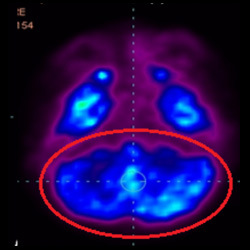

細(xì)胞治療前 PET CT 掃描顯示神經(jīng)組織中的藍(lán)/黑色區(qū)域,表明腦癱引起的大腦損傷。

細(xì)胞治療后,藍(lán)色和黑色區(qū)域減少,并且看到更活躍的區(qū)域。這表明損傷減少并改善了大腦功能。

這證明細(xì)胞療法是治療腦癱兒童安全有效的方法。細(xì)胞療法可以更新大腦損傷的核心,并且可以通過 PET CT 掃描來監(jiān)測大腦的改善情況。這些細(xì)胞療法與標(biāo)準(zhǔn)治療一起促進(jìn)腦癱兒童的生長和改善。